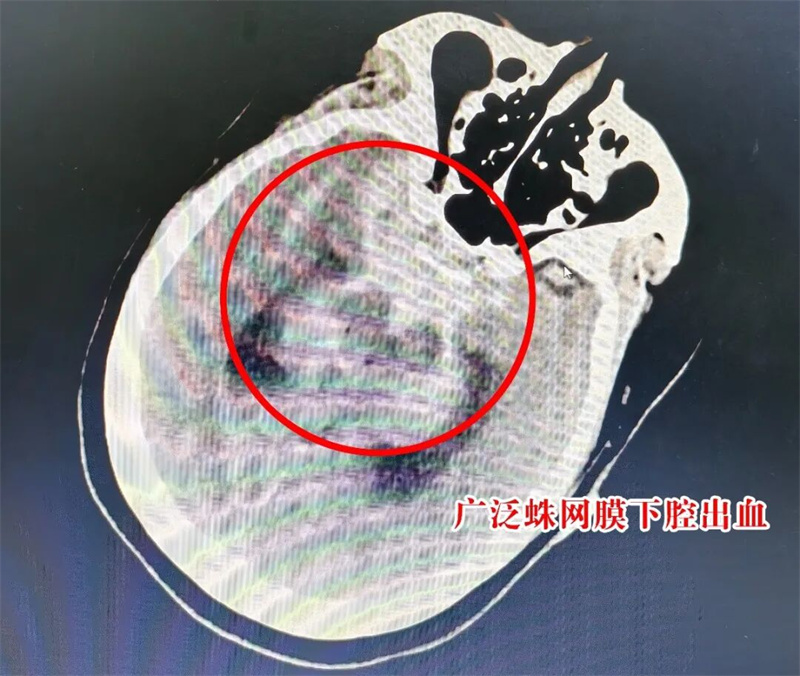

10月27日凌晨1时许,一声声呼救打破夜的沉寂……48岁的田女士(化名)被120急救车送到荆门市人民医院急诊科,她脸色苍白、神志模糊,双手紧紧抱着头。急诊医护一边询问病情——半小时前突发头晕、剧烈头痛、恶心呕吐,一边为她量血压——174/109m“查体高度怀疑脑血管问题!立即急查头颅CT。” 广泛蛛网膜下腔出血——最常见的病因就是颅内动脉瘤破裂。随后的头颈CTA(血管成像)提示右侧后交通动脉瘤、左侧后交通动脉瘤可能。

急诊CT提示:广泛蛛网膜下腔出血(脑室少许积血)